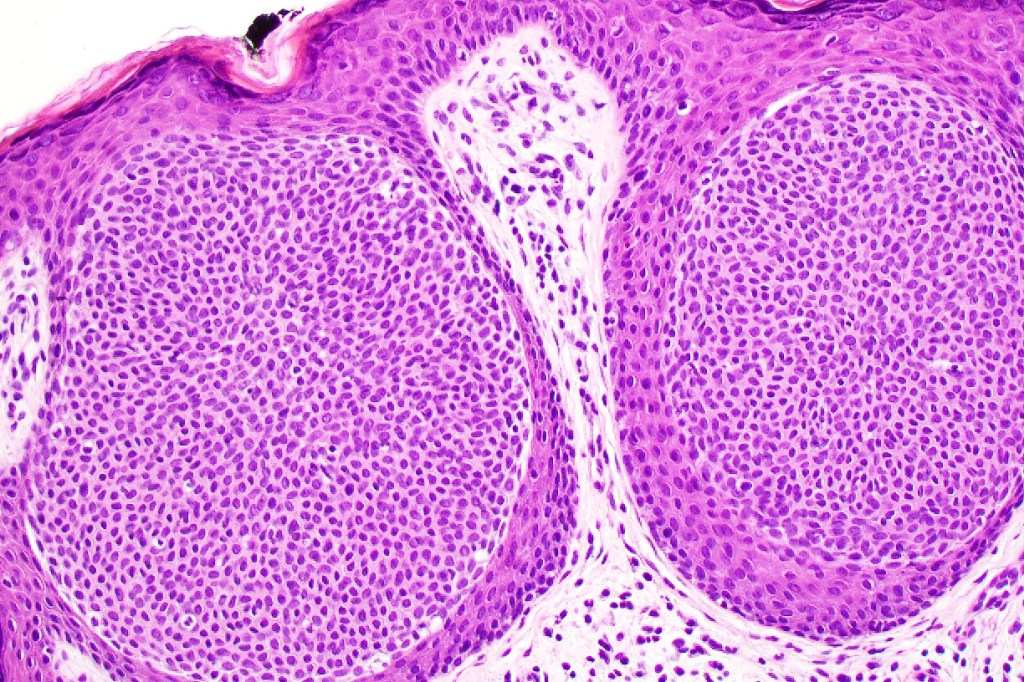

•In poroma, a dermal-centric tumor is associated with epidermal origin/continuity & is composed of small cells with vesical nuclei.

•Desmosomes often prominent

•No peripheral palisading or retraction artifact